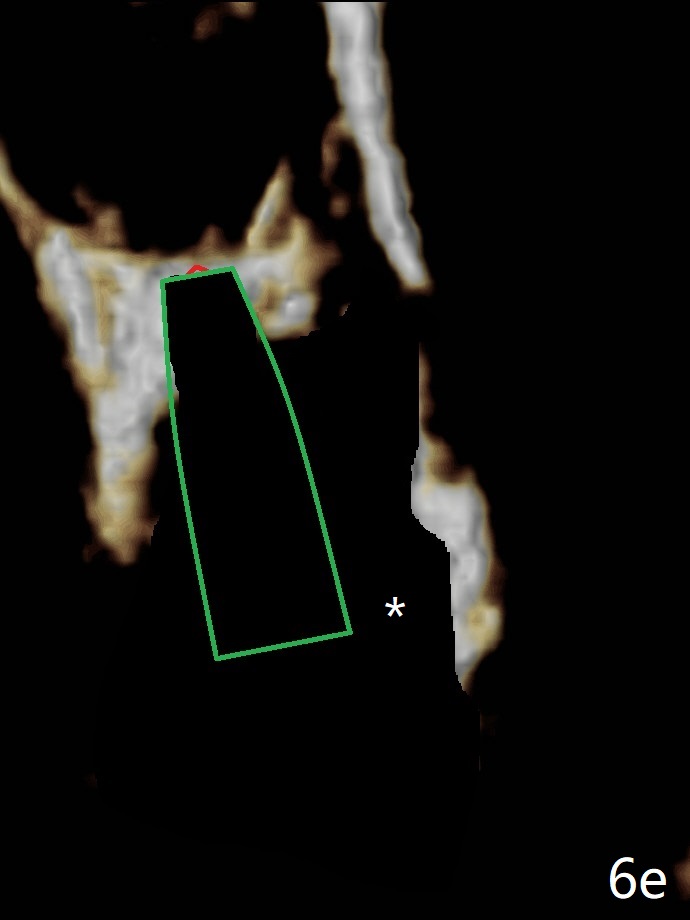

If the implant were placed first, the access to the buccal apical area (Fig.6e: *) would be smaller than when the last drill is in place.  Bone graft may be not placed deep enough (Fig.6f).